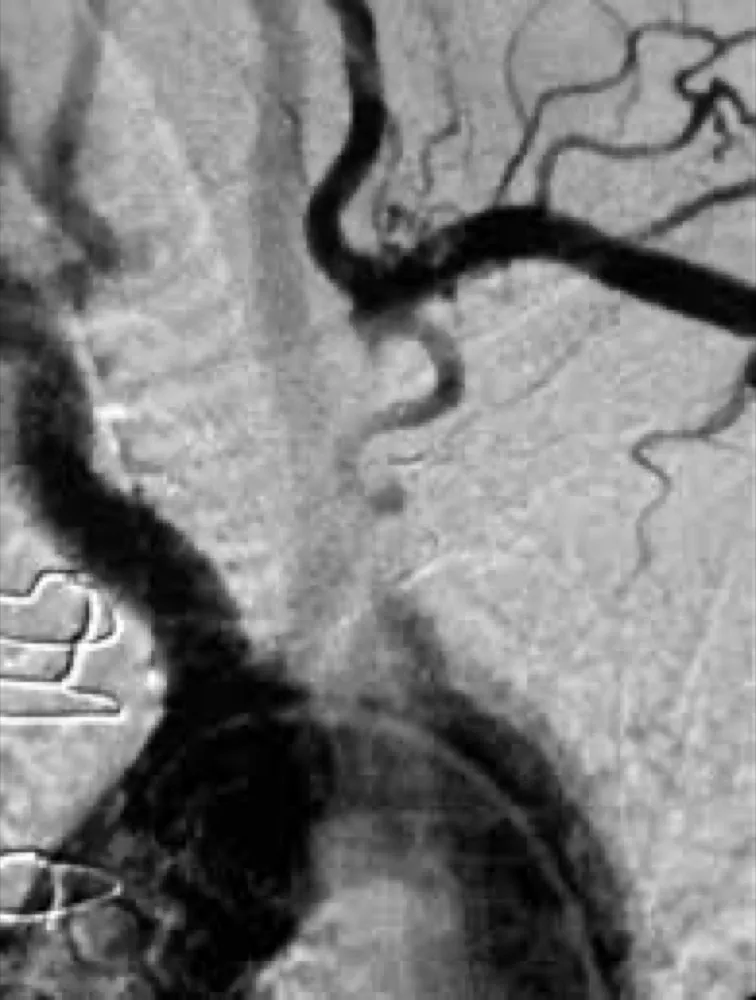

IRA + Icterícia: Um Caso que Exige Investigação Detalhada